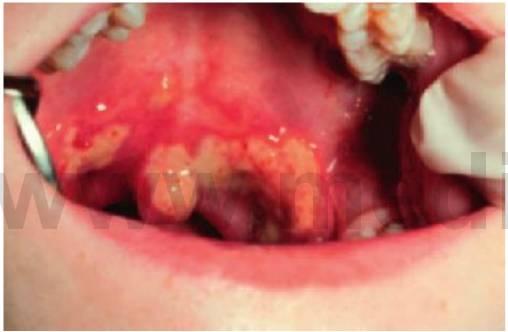

Herpangina y enfermedad pie-mano-boca

Estas infecciones están causadas por los virus del grupo Coxsackie A. Como con el herpes primario, las condiciones expuestas anteriormente tienen una fase prodrómica de fiebre no muy alta y malestar que puede durar varios días antes de la aparición de las vesículas. En la herpangina (fig. 8.3), suele encontrarse un racimo de 4 o 5 vesículas en el paladar, el arco palatogloso y la faringe, mientras que en la enfermedad pie-mano-boca se forman hasta 10 vesículas en dichas áreas, es decir, en manos, pies y cualquier región de la boca (fig. 8.3B). Las lesiones cutáneas aparecen en las palmas de las manos y las plantas de los pies, y están rodeadas por un margen eritematoso. Estas dos enfermedades suelen ser menos graves que el herpes primario y se curan en 10 días. Suelen presentarse de manera epidémica y afectan sobre todo a niños.